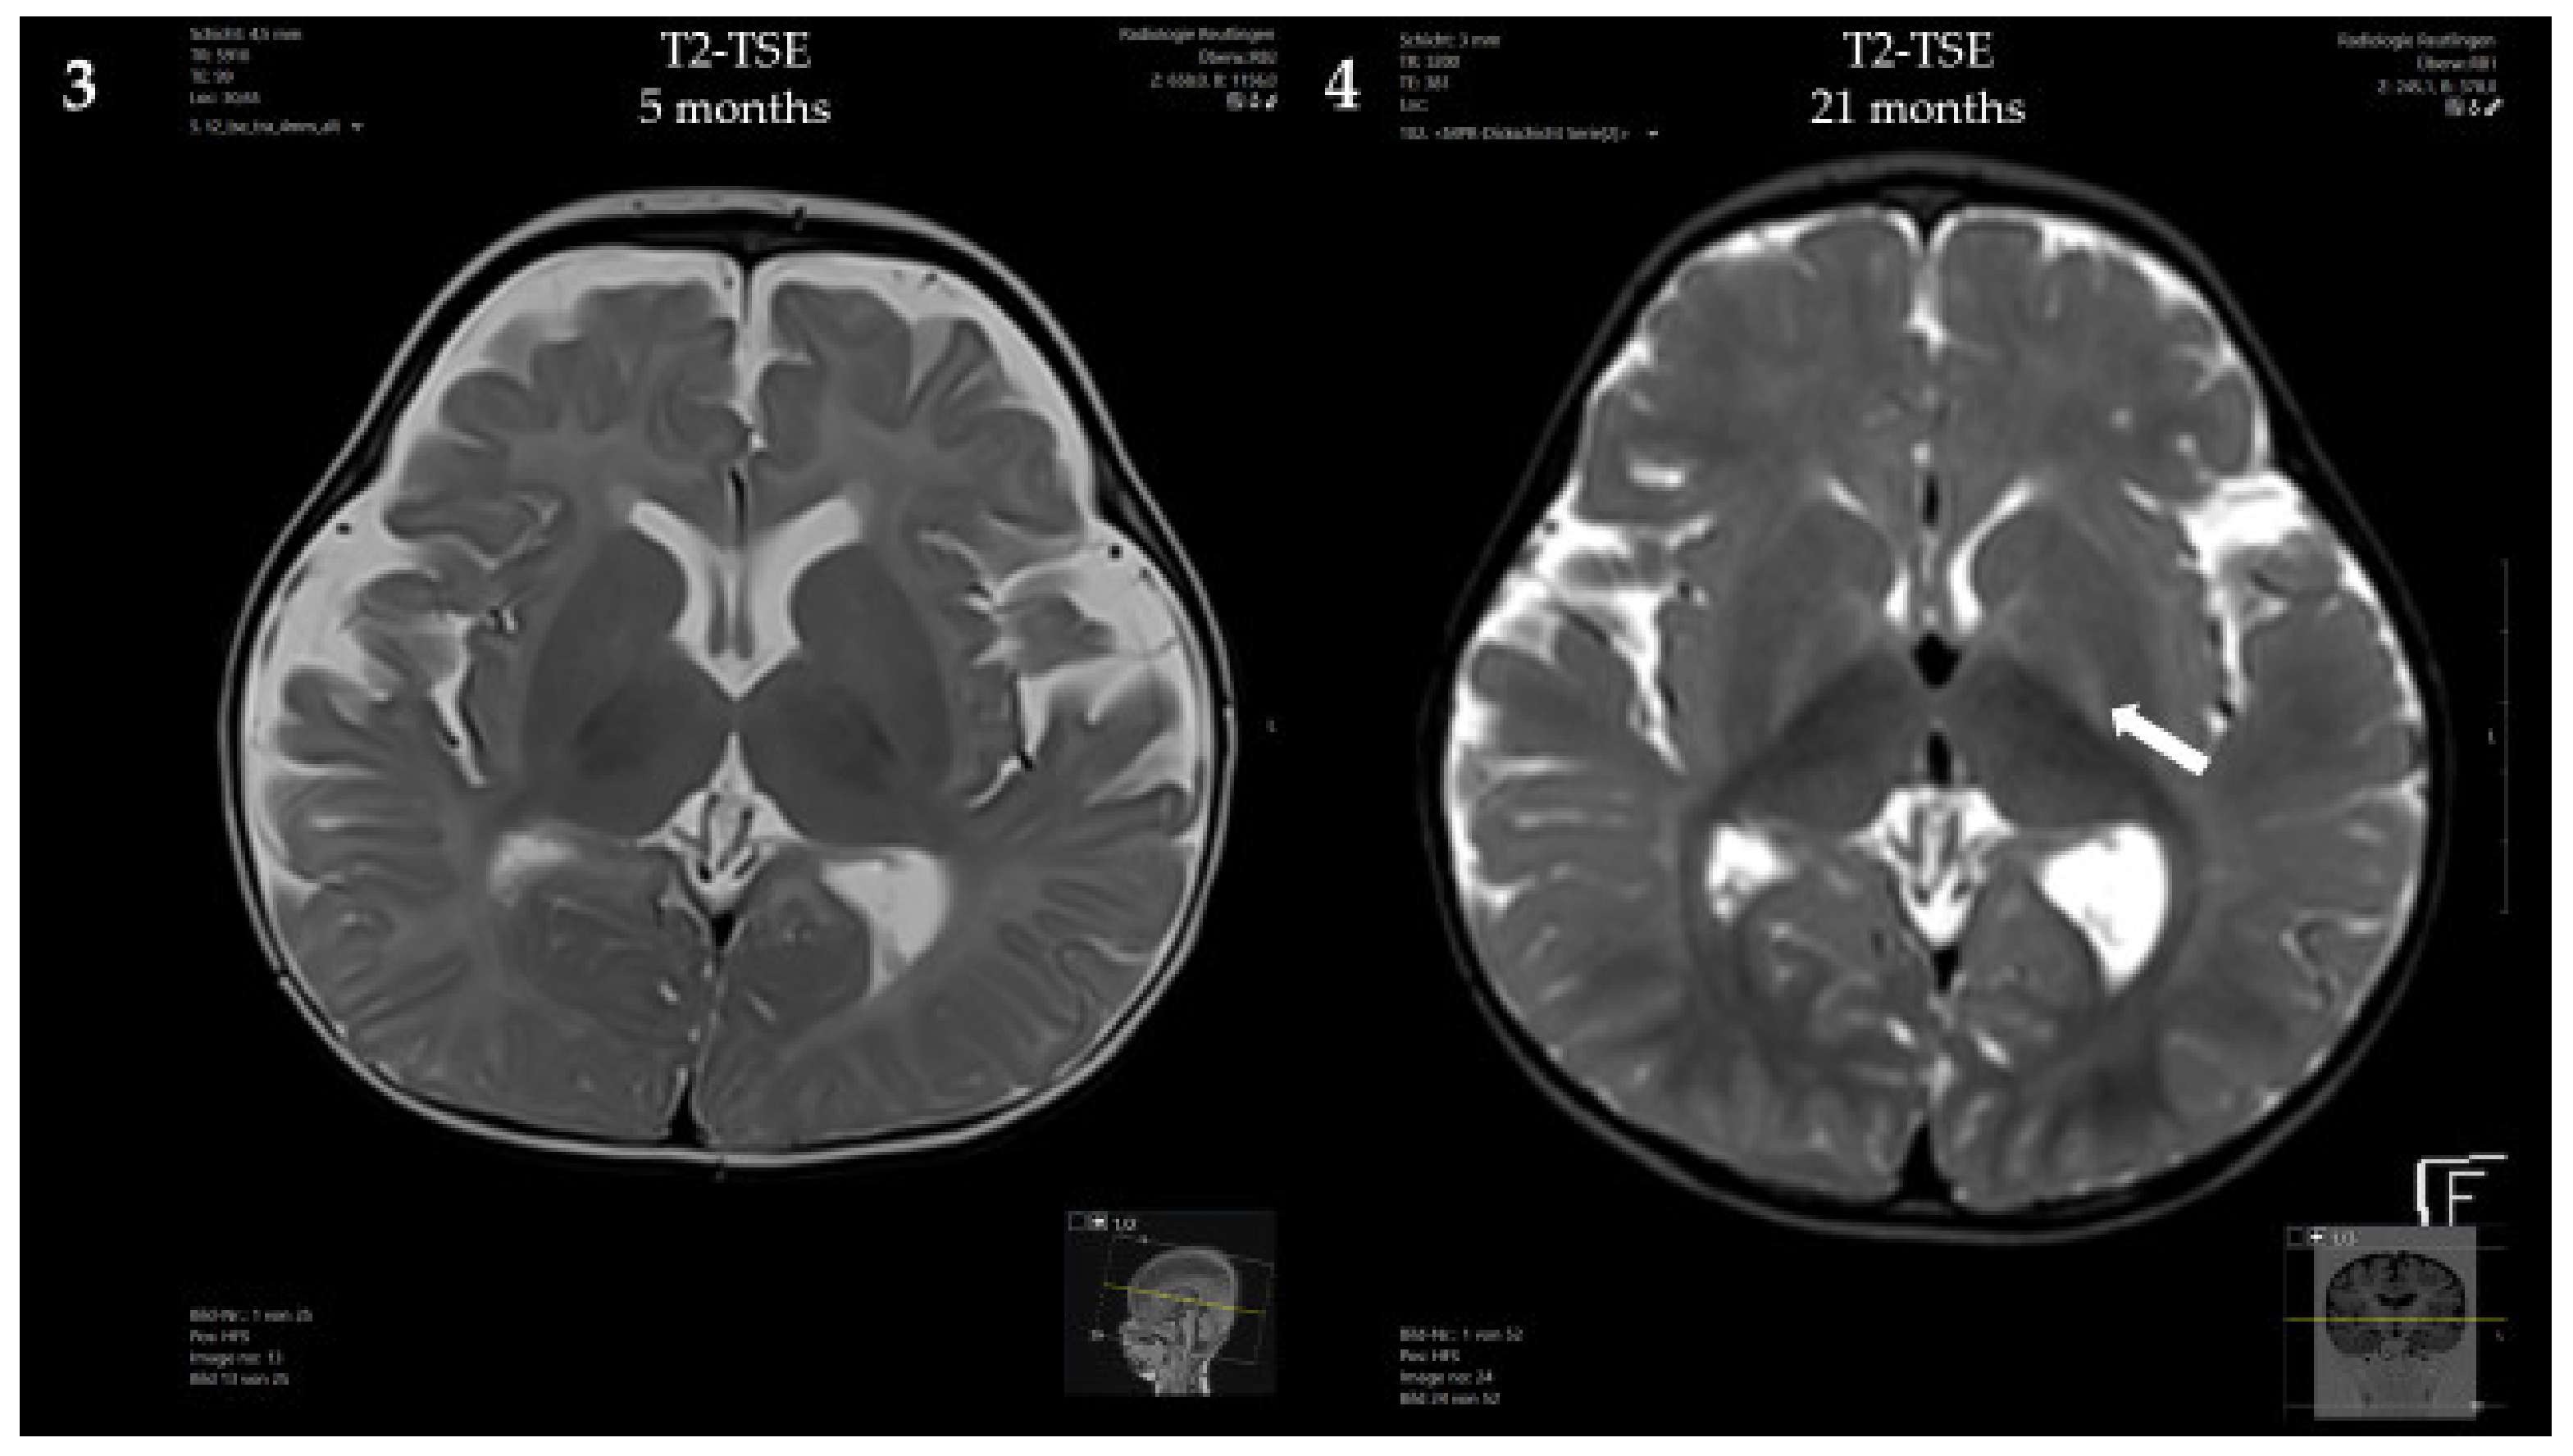

At 5 months, a brain MRI revealed mildly delayed myelination, dilated inner and outer cerebrospinal fluid spaces and mild periventricular diffusion interference (Figure 2). Clinically, the patient showed mild, predominantly motor, developmental delay (no hand support possible in prone position; no age-appropriate head posture; no turning of the child in prone and/or supine position) and mild muscular hypotonia. From 5 to 8 months of age, weight stagnation—likely due to decreased caloric intake—was observed. Dietary adaptation with an age-adequate calorie intake resulted in catch-up growth and normal weight at 14 months of age. Psychomotor development and muscle tone normalized.

Figure 2.

Brain MRI of the patient: (1,3) At 5 months, showing mildly delayed myelination, dilated inner and outer cerebrospinal fluid spaces and mild periventricular diffusion interference; (2,4) At 21 months, showing progressive diffusion impairment.

Psychomotor development at the age of 21 months was age-appropriate, and the patient showed normal growth under the Met-restricted diet (25 mg Met/kg/day). Met concentrations remained below 600 μmol/L. The concentration of AdoMet was normal (95.9 nmol/L, reference range 71–118 nmol/L). Despite the lack of neurological symptoms, a brain MRI at 21 months showed progressive diffusion impairment, but no structural abnormalities.